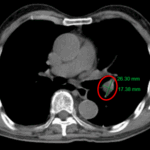

CASE LÂM SÀNG: CHẨN ĐOÁN BỆNH NHÂN MẮC HAI UNG THƯ: GIST RUỘT NON VÀ UNG THƯ TUYẾN GIÁP TẠI TRUNG TÂM Y HỌC HẠT NHÂN VÀ UNG BƯỚU, BỆNH VIỆN BẠCH MAI

Ca lâm sàng